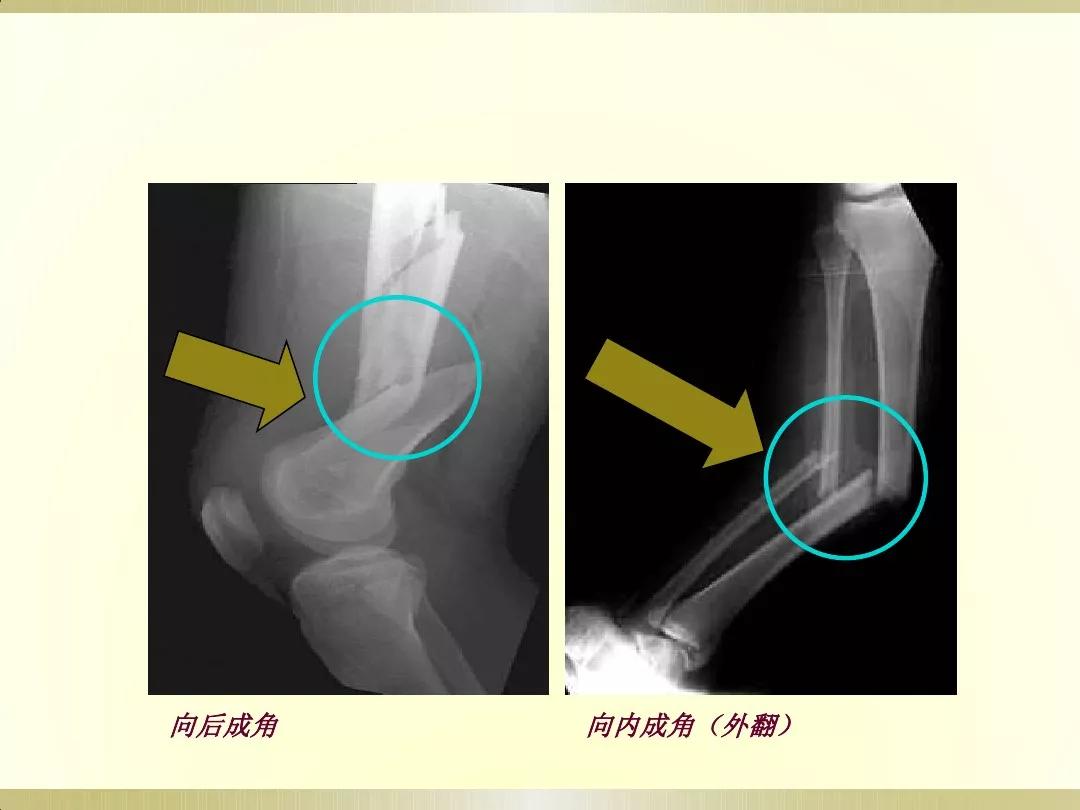

X线摄片就是通过让一种有能量的电磁波,即X射线透射过身体不同组织结构,在胶片上形成明暗或黑白对比不同的影像,被称为X线摄片。

医生可以通过X射线检查来识别各种组织,并根据阴影的形态和浓淡变化来分析其是否属于正常。这很像我们日常所说的拍照片,出来的图像是平面的。

检查部位:X线可以检查身体的许多部位。通常用于检查胸部(大致了解情况)、骨骼、肌肉或脏器,以及发现体内的气体,也可探查金属物体。